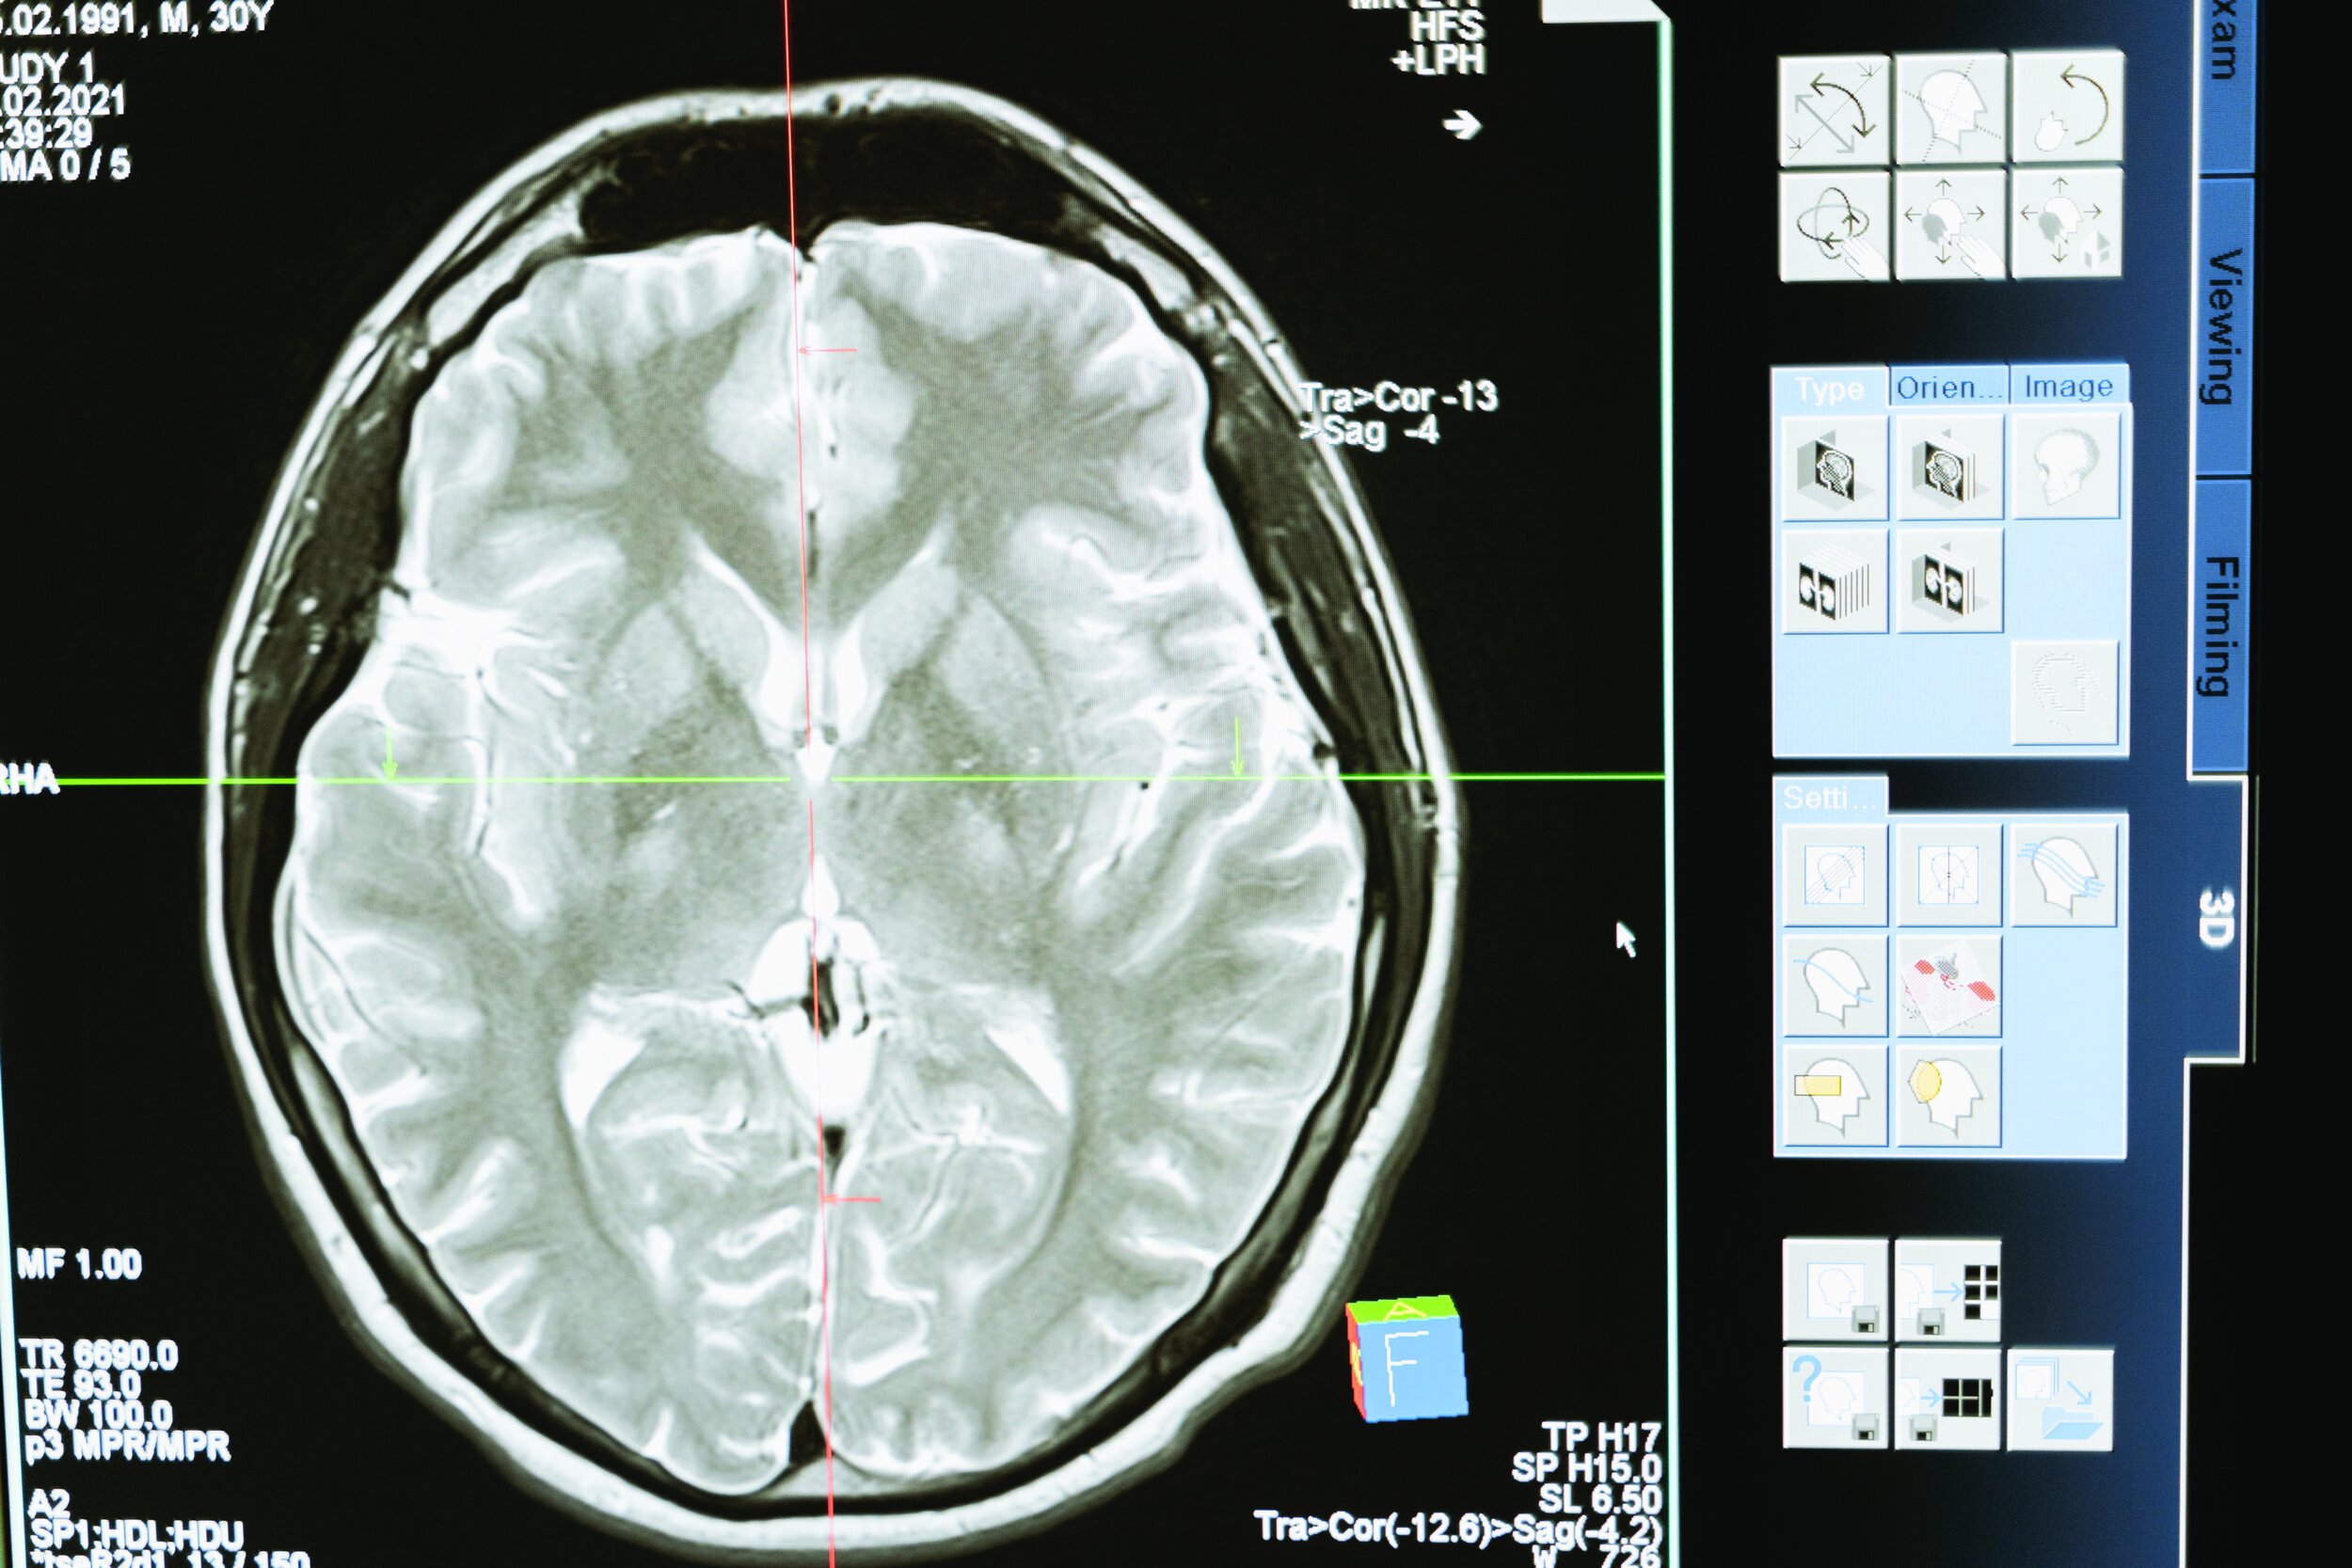

Neurologists provide a critical analysis and interpretation of medical evidence within the legal context. This may involve reviewing medical records, diagnostic tests, and other relevant documentation to form an informed opinion on the neurological aspects of a case.